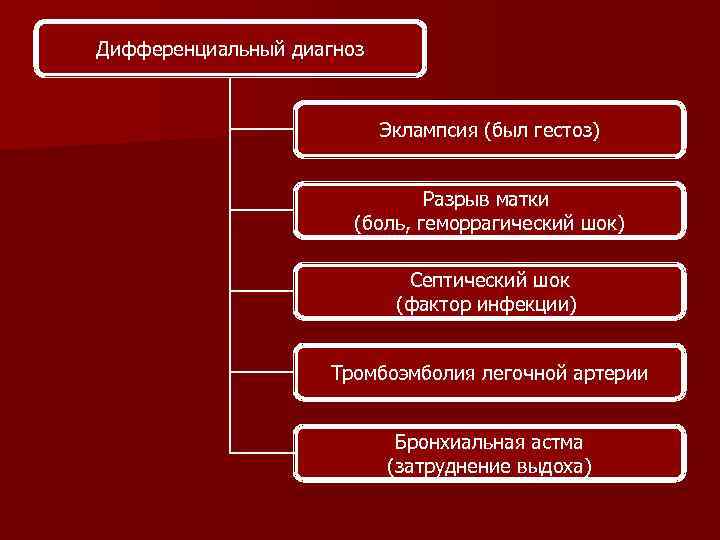

Дифференциальный диагноз Эклампсия (был гестоз) Разрыв матки (боль, геморрагический шок) Септический шок (фактор инфекции) Тромбоэмболия легочной артерии Бронхиальная астма (затруднение выдоха)

Дифференциальный диагноз Эклампсия (был гестоз) Разрыв матки (боль, геморрагический шок) Септический шок (фактор инфекции) Тромбоэмболия легочной артерии Бронхиальная астма (затруднение выдоха)